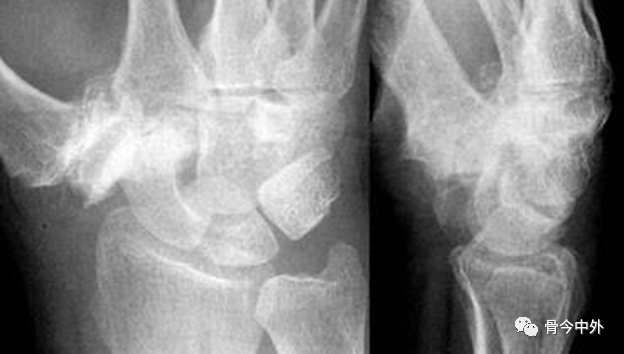

图35

- 侧位片

- 可以确定为月骨周围脱位伴舟骨、尺骨茎突骨折。月骨呈三角形仅为月骨倾斜。

- 可见月骨掌侧极骨折(圆圈),脱位易复发。